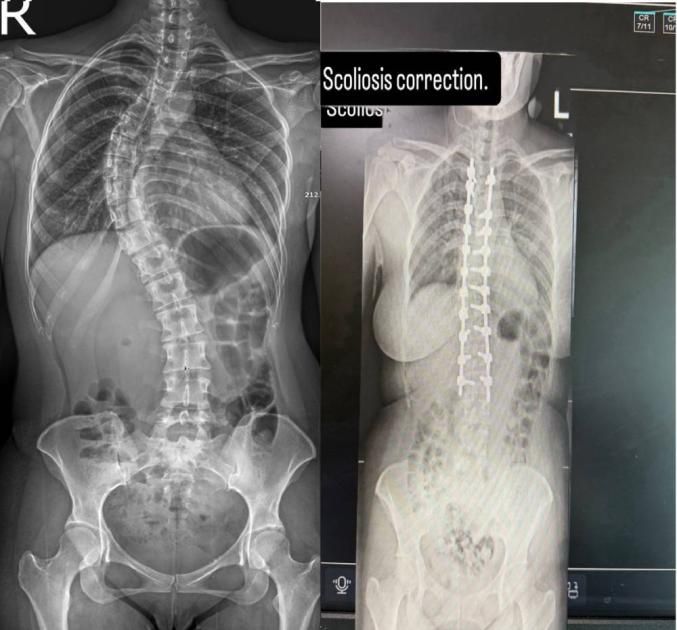

حقق مركز جراحة العمود الفقري في مستشفى السعودي الألماني دبي، إنجازاً طبياً متقدماً، بعد نجاحه في إجراء واحدة من أدق وأعقد عمليات تصحيح اعوجاج العمود الفقري (الجنف) لمريضة عانت منذ طفولتها تشوّهاً حاداً ومهملاً، تطوّر على مدى ثلاثة عقود إلى تيبّس هيكلي كامل في الفقرات، ما تسبب في آلام مزمنة وقيود حركية أثّرت بشكل مباشر في جودة حياتها.

ومثلت الحالة تحدياً طبياً بالغ الدقة، نظراً لتحوّل الاعوجاج المزمن إلى تشوّه صلب في بنية العمود الفقري، ما جعل أي تدخل جراحي محفوفاً بالمخاطر ويتطلب خبرات تخصصية عالية وتخطيطاً دقيقاً وفق أفضل الممارسات الجراحية العالمية. وبقيادة البروفيسور حازم فريد، استشاري جراحة العمود الفقري، تم تنفيذ بروتوكول جراحي متقدم نجح في فكّ التيبّس الهيكلي وإعادة التوازن الطبيعي لمحور الجسم.

واعتمد الفريق الجراحي خلال العملية، التي استغرقت نحو ثلاث ساعات ونصف الساعة، على تقنية القصّ العظمي لتحرير الفقرات المتصلبة وإعادة بنائها بدقة عالية. ولضمان سلامة النخاع الشوكي، جرى توظيف نظام متطور للمراقبة العصبية الفورية، الذي وفّر قراءة لحظية للإشارات العصبية طوال مراحل التصحيح.

واستعادت المريضة استقامة قامتها وقدرتها على الوقوف والمشي بصورة طبيعية بعد ساعات قليلة من العملية، منهية رحلة طويلة من الألم والتيبّس والقيود الحركية. ولم يقتصر الأثر على التصحيح الجسدي فحسب، بل انعكس بشكل إيجابي على حالتها النفسية وقدرتها على العودة إلى ممارسة حياتها اليومية بثقة واستقلالية.